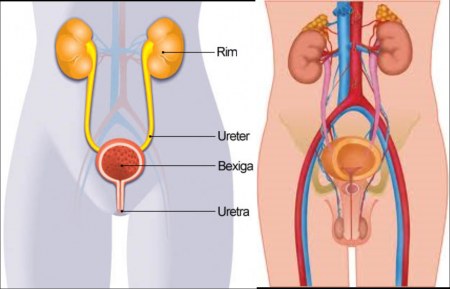

Urologia é uma especialidade cirúrgica da medicina que trata do trato urinário de homens e de mulheres e do sistema reprodutor dos homens. Os médicos que possuem especialização nesta área são os urologistas, sendo treinados para diagnosticar, tratar e acompanhar pacientes com distúrbios urológicos. Os órgãos estudados pelos urologistas incluem os rins, ureteres, bexiga urinária, uretra e os órgãos do sistema reprodutor masculino (testículos, epidídimos, ducto deferente, vesículas seminais,...